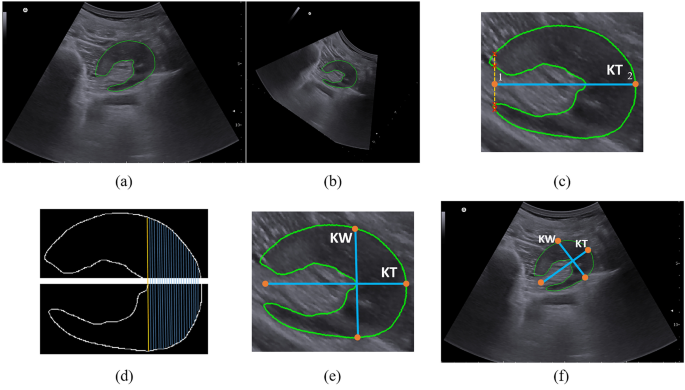

Post-processing of axial images

We applied an algorithm to calculate kidney thickness using the axial plane, which some radiologists prefer. Figure 3 shows that the kidney thickness was measured in the axial plane as the maximum length parallel to the hilum. After the kidney segmentation, the major axis of the mask was calculated using the first eigenvector of the principal component analysis (PCA). Then, the mask was rotated horizontally using the angle achieved from eigenvectors (Fig. 3b). When the level of the hilum is on the left, the rightmost point of the mask represents the kidney border terminal and vice versa. This point is shown as point 2 in Fig. 3c. Point 1 was determined by finding the first line that passes through four points in the mask contour and assigning the middle point as the point.

Post-processing of axial view image. (a) Segmentation of axial image, (b) rotation of the image to make it horizontal, (c) estimating kidney thickness (KT) by finding two terminal points, (d) separation of upper and lower parts of the mask and finding the longest distance, (e) kidney width (KW) and KT, and (f) KW and KT in the original image.

The upper and lower parts of the contour were separated to measure the kidney width. For each point in the upper part, the nearest point in the lower part was found. Therefore, the longest distance between these pairs of points was determined as the kidney thickness (Fig. 3d, e). Finally, the rotation algorithm is applied in the opposite direction to achieve the real places of the determined points, as shown in Fig. 3f.